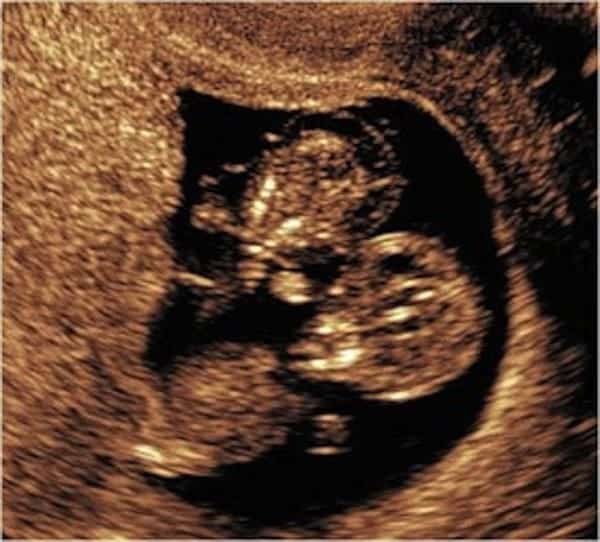

Οι γιατροί έμειναν άφωνοι όταν είδαν τους πλεγμένους ομφάλιους λώρους. Τα κορίτσια είχαν επιβιώσει από μια φρικιαστική εμπλοκή, με έναν πραγματικό κόμπο να έχει δημιουργηθεί σε ένα σημείο. Η Kate τα γέννησε ακριβώς στην ώρα τους. Δημοσίευσε αυτή τη φωτογραφία στο Facebook και έχει γίνει πλέον viral.